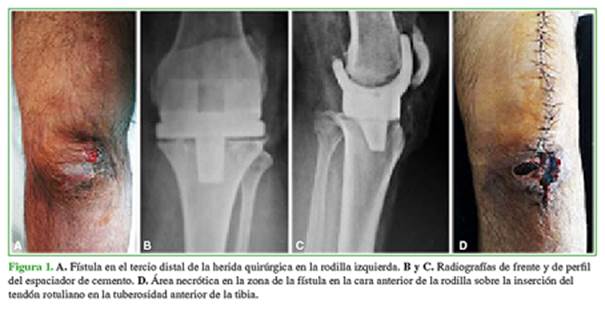

Con parámetros clínico-humorales de remisión de la infección3 y tras haber logrado una cobertura y una cicatrización adecuadas, se realizó la conversión a prótesis de rodilla en enero de 2018 (Figura 7).